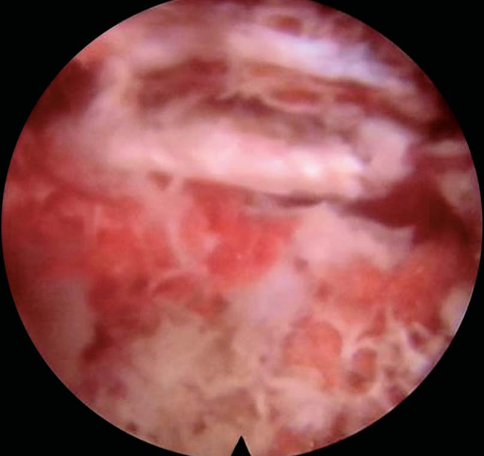

镜下完成标志:硬膜囊的波动及L5神经根减压游离,椎管内减压充分(图29)。

图29 镜下操作完成标志神经根漂浮试验阳性